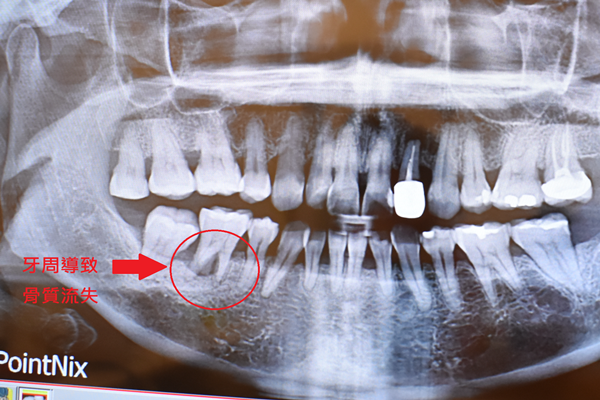

指著X光片游醫師比劃那顆發炎的臼齒,

片子上白白的地方是牙齒骨頭

臼齒跟骨頭之間已經泛黑

泛黑?!對!頂著滿頭問號問號??

後來才知道泛黑表示牙周細菌會造成骨頭被侵蝕無法跟牙根緊密相連

X光片上牙根幾乎已經懸空浮起來

難怪總覺得那顆臼齒有點搖搖晃晃